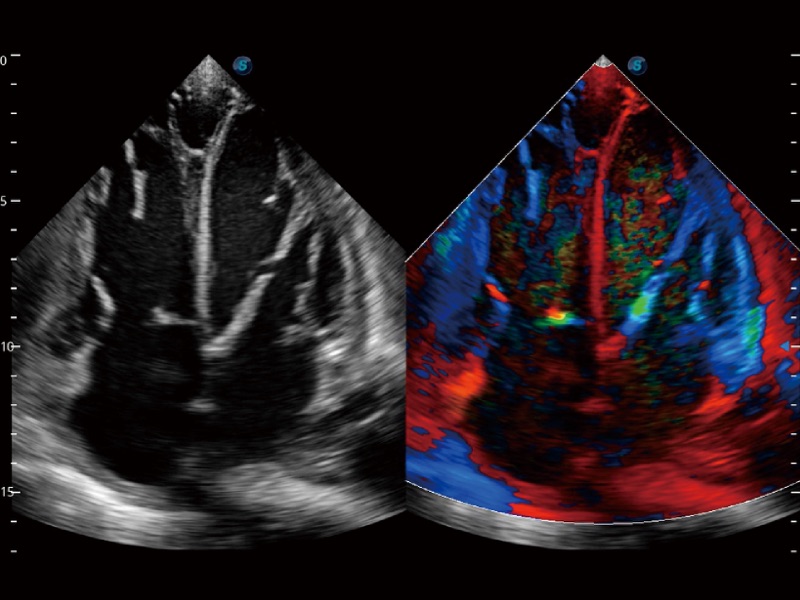

• SR Flow

Como nueva tecnología innovadora, SR Flow mejora la capacidad de detectar señales de flujo de baja velocidad. También mejora la resolución espacial y sortea el sobreflujo para presentar a los usuarios información hemodinámica real.

A4C con TDI